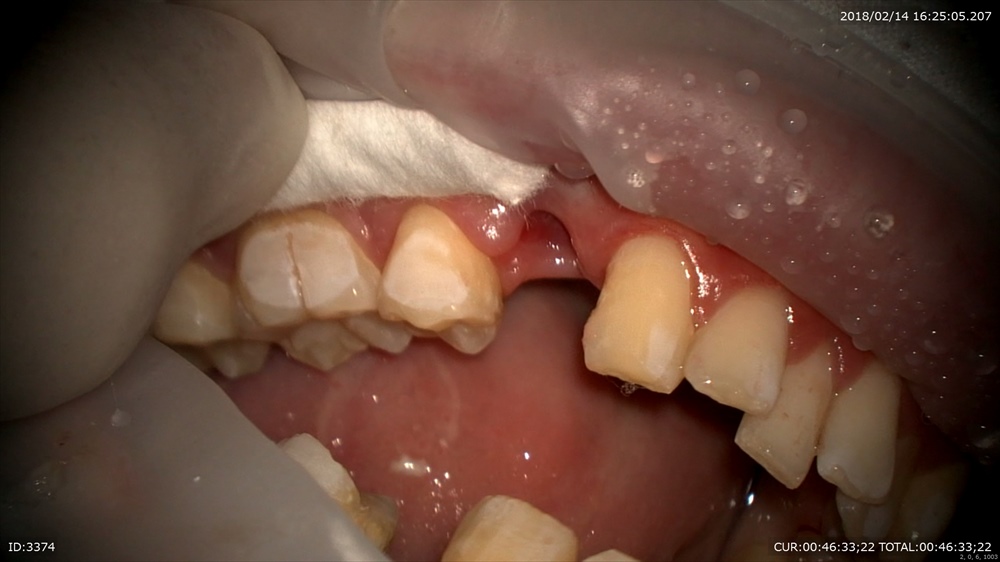

矯正の装置装着の初日の男の患者さま。歯並び良くなったら更にイケメンに!!なりますね。精密な矯正診断により上下で4本の抜歯により矯正治療を行う事が決まりました。当院では

抜歯、お掃除、装置装着、今日はミニスクリューを2本。これを同時に行います。

当院ではこの方法を行っております。総合歯科ならではです。

抜歯後、お掃除